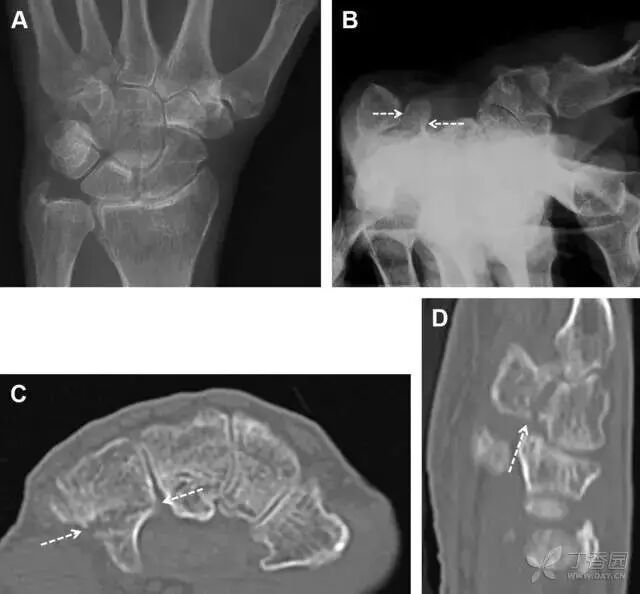

桡骨远端骨折

常规进行前后位、侧位、斜位 X 线检查,对于大多数桡骨远端骨折来说不容易漏诊;但是对于无移位的骨折,特别是桡骨茎突骨折,容易漏诊。桡骨茎突骨折是一斜行的骨折,常累及关节面,常发生于轴向应力或直接打击。

图 1 57 岁女性,摔倒后手掌撑地,桡骨茎突压痛。(A~C)前后位、斜位、侧位片示软组织肿胀(*)和发丝样骨折(白色箭头);(D~F)2 周后,前后位、斜位、侧位片示骨折线显明,由于新骨痂沉积而呈现透亮线与硬化线并存;(G~I)另一患者,桡骨茎突骨折在前后位及侧位片上显示不明显,而在斜位片显示更清楚。

舟状骨骨折

舟状骨骨折 60%~70% 发生于腰部,15% 发生于近极, 10% 发生于远极, 8% 发生于远端关节面。除了常规的前后位、侧位、斜位片外,还需要拍专门的舟状骨位片(腕关节尺偏,以舟状骨为中心的腕关节前后位片),特别是鼻烟壶有压痛时。

图 2 舟状骨骨折 (A、B)第 1 例患者,舟状骨远极关节内骨折(白色箭头),斜位片显示较清楚(B);(C、D)第 2 例患者,舟状骨腰部骨折(虚线箭头),斜位片显示较清楚(D);(E~H)第 3 例患者,舟状骨近极骨折,常规 X 线片均未看到骨折,而在舟状骨位片上才能见到骨折(虚线圆)。